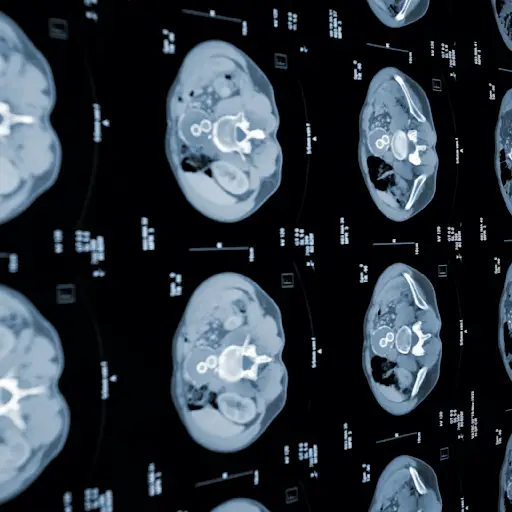

纽约长岛亨廷顿医院结肠外科主任David Rivadeneira医学博士说:“在分期阶段,我们做了大量的影像学研究以寻找更多的线索。”一种CT扫描(CT代表“计算机断层扫描”)使用X射线进行详细的横截面图像,显示癌症是否已蔓延到附近淋巴结-immune系统腺体,可帮助癌症旅行 - 或者到其他器官。

一个超声依靠声波来检测附近的器官是否有癌症扩散。磁共振成像(MRI)使用无线电波和强磁铁来检测肝,大脑和脊髓。在一个PET扫描(正电子发射断层摄影术),在结肠癌中很少使用,将一种聚集在癌细胞中具有轻微放射性的糖注射到血液中,观察它的移动方向。